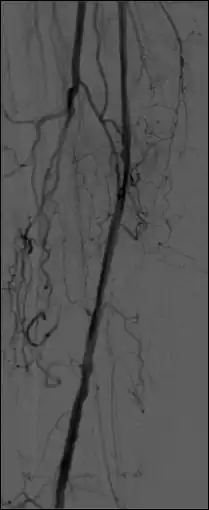

- The representation in Figure 7.12 demonstrates the principle in action. A single projection is back-projected to give a dark stripe across the entire image plane - see panel (a). As the phantom is scanned from different angles and the projections back-projected onto the image plane from many directions, an image of the radio-opaque object begins to emerge - see panel (b). As the number of projections increases, the quality improves but there will always remain streaking as seen in panel (c). A certain amount of spurious background information remains which can severely degrade the quality of reconstructed images. In mathematical terms, the image is blurred because of a convolution with a 1/r functional dependence on distance, r. In other words, the point spread function (PSF) has a 1/r dependence which is totally attributable to the back projection process.

- Image quality can be improved substantially using a modified form of back-projection called Filtered Back Projection (FBP). In this technique - see Figure 7.13 - projection data is first filtered spatially to account for the effect of sudden density changes which cause the streaking in simple back-projection. The filter is referred to as a convolution filter or kernel. The procedure can be performed in the spatial frequency domain using Fourier Transform (FT) methods or directly with spatial domain processing. After the convolution process, the data for each projection is inverse Fourier transformed before the back projection computation is undertaken. In practice the task of image reconstruction is performed using special array processors and dedicated hardware, which aids in speeding up the reconstruction task.

- A choice of filters can generally be selected to enhance either soft tissue features in the image or bone detail. Indeed, the image can be post-processed using a different filter after the scan has been completed if needed. Images can be generated to enhance bone detail or display subtle low contrast masses without the need to re-scan the patient. The filter choice therefore has a major impact on image quality. The two most common filters used in X-ray CT are those due to Ramachandran & Lakshminarayana (commonly called the Ram-Lak) and Shepp & Logan. Viewed in spatial frequency space, the former is essentially a ramp filter with a cut off frequency and the latter combines a smoothing filter with the ramp to attenuate high frequency noise. The ramp filter compensates for the artefacts introduced by the simple back projection process but does not compensate for the increasing noise content of the data with increasing frequency. Images of an axial tomogram reconstructed with a soft tissue and with a bone algorithm can be seen in Figure 7.14.